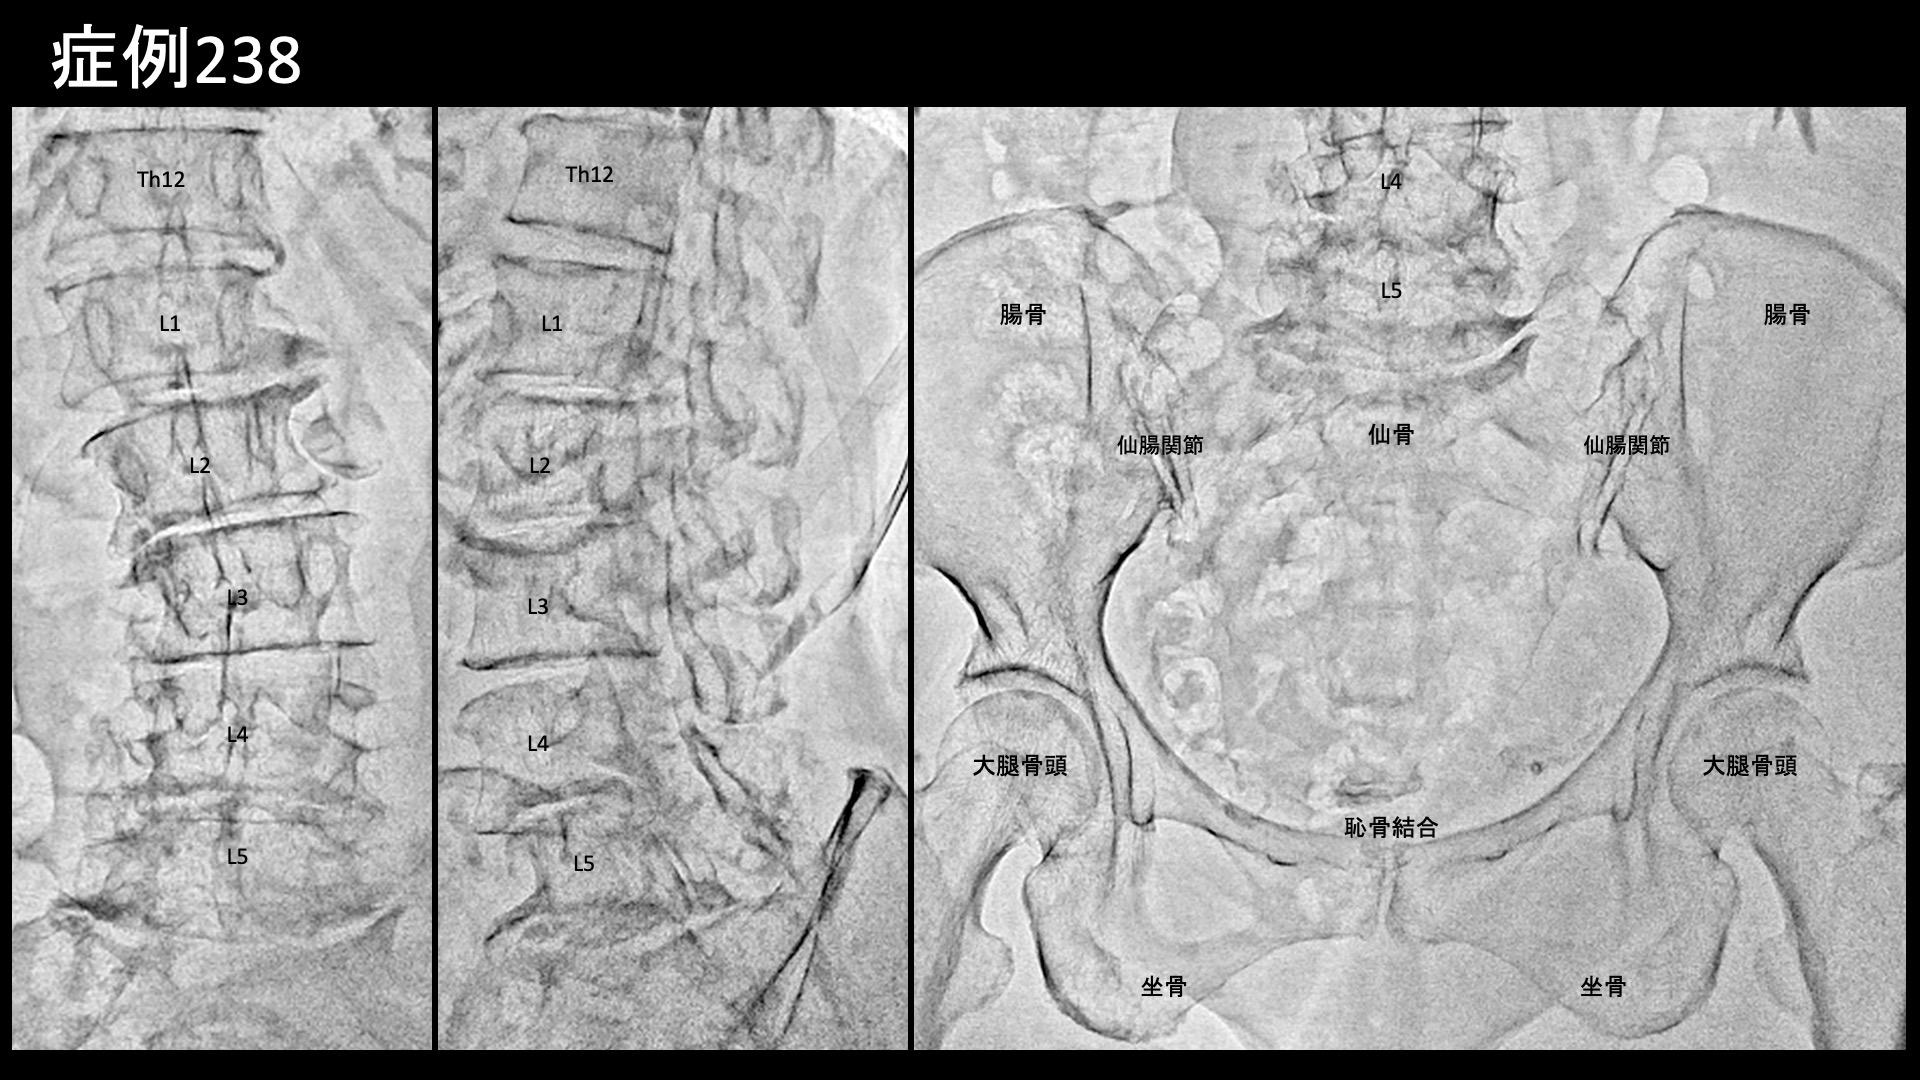

腰:椎間関節炎など 【80代:女性】新型コロナウイルス感染を契機に悪化した変形性腰椎症による腰痛/坐骨神経痛(新型コロナウイルス感染、変形性腰椎症、腰痛、坐骨神経痛) 2025.09.19 鴨井院長による動画解説 受診までの経過 20年前にゴルフ中に腰を痛めて以来、慢性的に腰痛を繰り返すようになりました。坐骨神経痛と診断され、ブロック注射などの治療を受けてきました。5年前から悪化してきましたが、新型コロナウイルスに感染したことをきっかけに痛みがさらに激しくなりました。ブロック注射も効かなくなってしまいました。仰向けで寝る分には痛みはない一方で、立位や歩行時に、特に左側の痛み・しびれが辛く感じていました。 診察時の所見 レントゲンでは一見して高度の腰椎変形を認め、歩くのもままならないくらいのもっと強い症状が出ていても不思議ではないくらいでした。腰の動きを確認すると、前屈で疼痛が誘発され、全ての動作において中等度以上の可動域制限がみられました。股関節の動きは保たれていました。後上腸骨棘では比較的強い圧痛が認められました。その他の診察所見と併せて、左坐骨神経痛を伴った変形性腰椎症、仙腸関節障害と診断しました。構造的異常は強いものの、神経障害としては固定化されておらず治療による一定の改善が期待されました。治療適応と判断し、モヤモヤ血管(病的新生血管)に対する運動器カテーテル治療(微細動脈塞栓術)を受けていただきました。 治療の所見 腰椎レベル~股関節周囲レベルにかけて広範囲の治療を行いました。左腰動脈、腸腰動脈などで特に再現痛を認めました。 *再現痛とは、薬液投与時に普段の痛みが一定程度再現される現象です。責任血管の同定のための参考とします。特に腰臀部領域では、モヤモヤ血管を視認することが困難なことが多いため再現痛の確認は重要です。 治療後の経過 治療後3-4日はとても楽でしたが、その後再燃し、午前中は楽に感じるものの、治療後2週間ではまだ大きく変わりはありませんでした。治療後1ヶ月、鼠径部に感じていた痛みは無くなりました。歩く時の痛みについてはまだ一部の改善にとどまっていました。治療後2ヶ月、入室時のご様子から既にこれまでと違っていて、歩容が改善してスムーズに入室されました。強い痛みは半減し、立ち上がりの際には痛むものの、歩いている内に無くなるようになりました。寝がえりの際の痛みも無くなりました。治療後2ヶ月半を過ぎる頃から、左側の痛みはほとんど無くなってきました。治療後5ヶ月時点でも痛みなく良い状態を維持できています。本症例では、長年くすぶり続けた慢性炎症が新型コロナウイルス感染を機に悪化したことが考えられました。高度の腰椎変形があり治療の有効性に懸念がありましたが、カテーテル治療は『強い炎症にはよく効く』という側面があります。感染を契機に悪化した症状には有効な可能性が高いです。 坐骨神経痛の詳しい病状説明はこちら 【90代:女性】ここにできたら要注意!超高齢者に生じた頭部・顔面の帯状疱疹後神経痛(発症1ヶ月) (帯状疱疹後神経痛) 前の記事 【70代:男性】夜間痛がその日のうちに改善!強い炎症を伴った変形性膝関節症に対する運動器カテーテル治療(変形性膝関節症) 次の記事